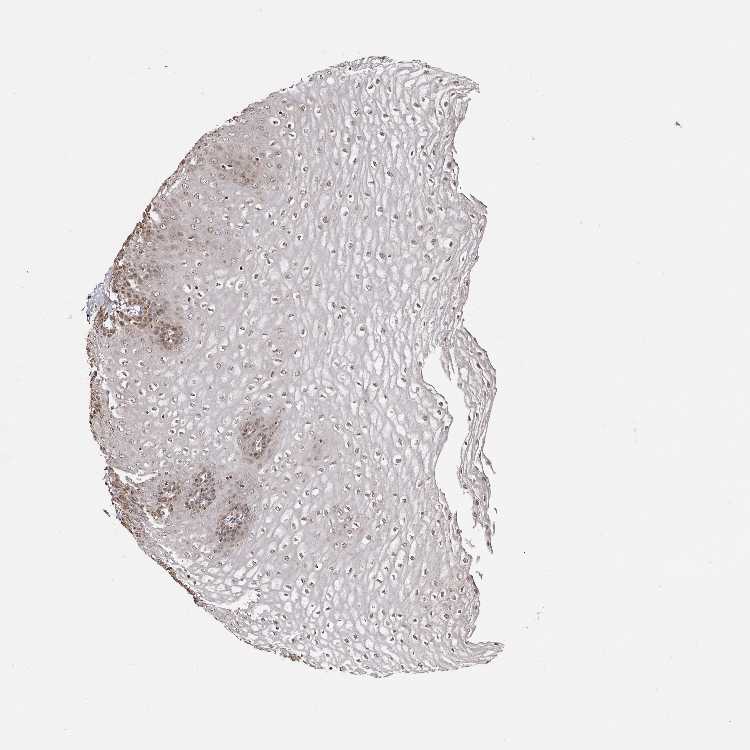

ESOPHAGUS - Antibody stainingi

Antibody staining in the annotated cell types in the current human tissue is reported as not detected, low, medium, or high, based on conventional immunohistochemistry profiling in selected tissues. This score is based on the combination of the staining intensity and fraction of stained cells.

Each image is clickable and will lead to virtual microscopy that enables deeper exploration of all samples and also displays staining intensity scores, fraction scores and subcellular localization as well as patient and tissue information for each sample.

Antibody HPA028579Antibody HPA028584Antibody HPA028592

Squamous epithelial cells HighMediumLow